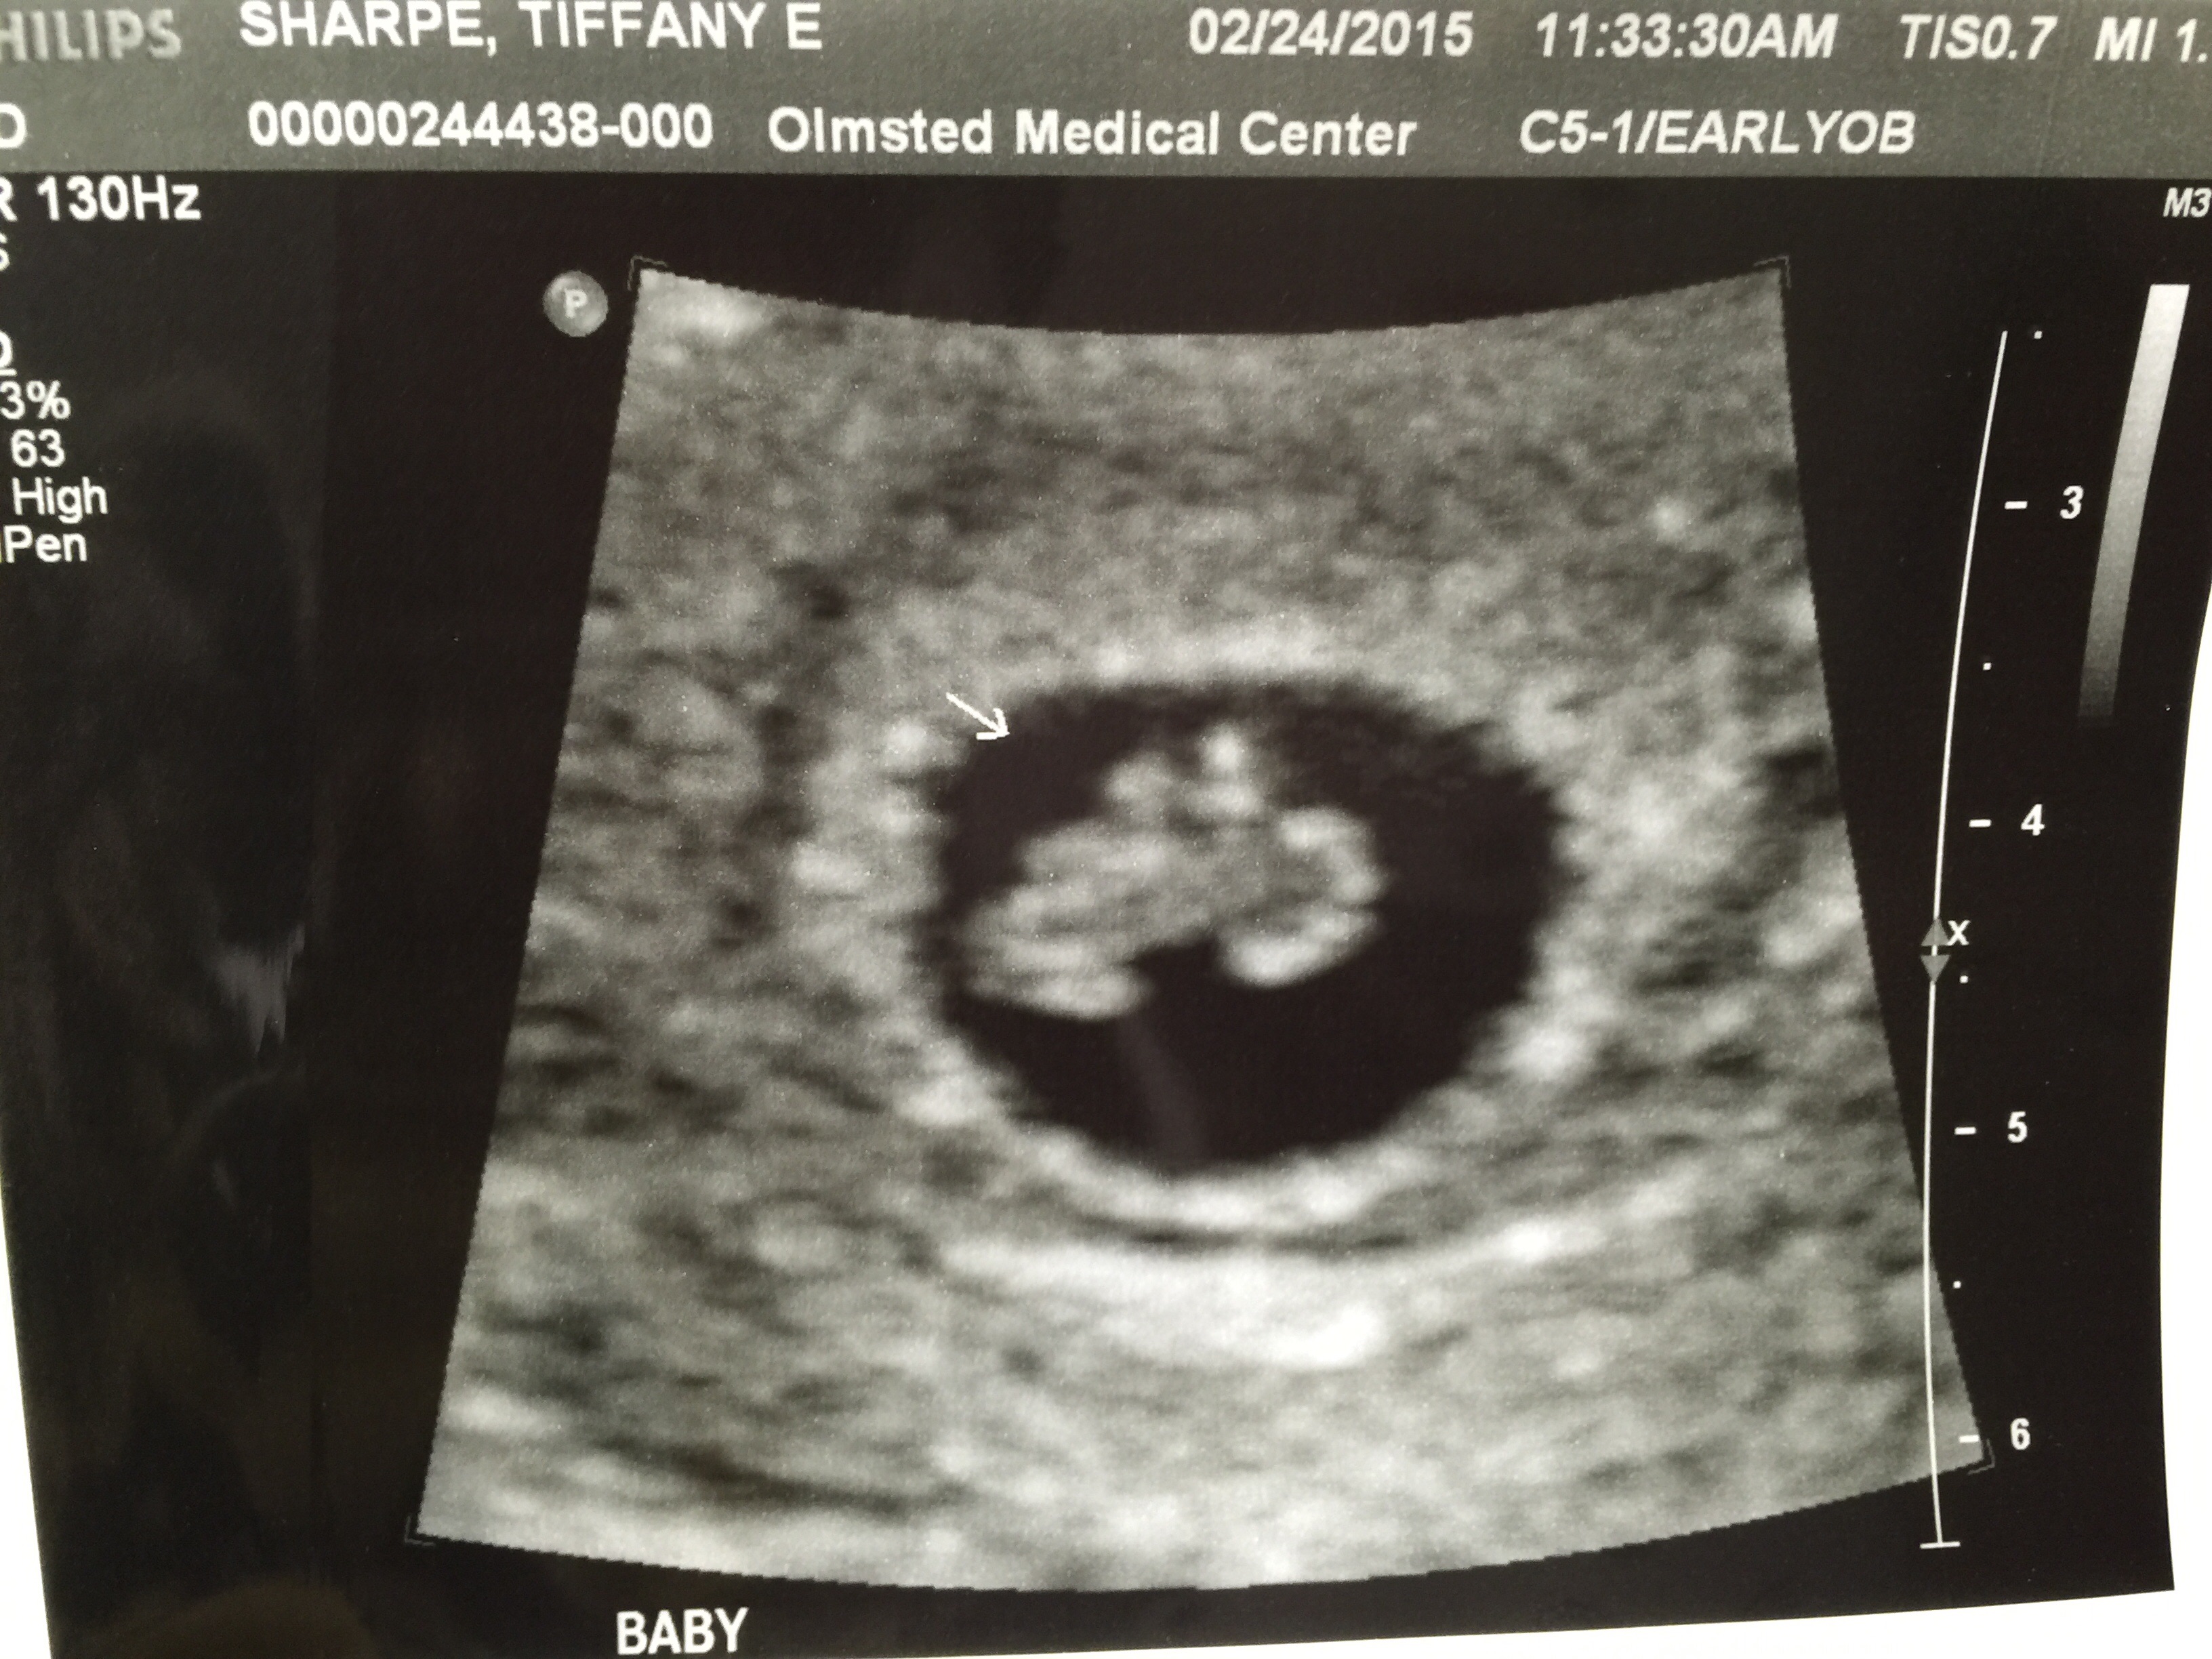

• 6 weeks 4 days